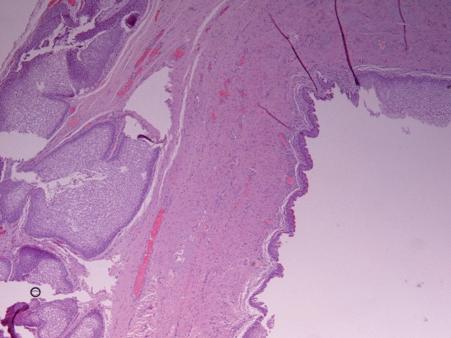

before surgical removal. Histological examination of the removed mass confirmed the diagnosis of a cyst lined by metaplastic squamous epithelium and pseudostratified columnar epithelium. Patient regained the ability to urinate after the removal of catheter.

Histological examination of the removed mass confirmed the diagnosis of cyst lined by metaplastic squamous and pseudostratified columnar epithelium.

pseudostratified columnar epithelium.